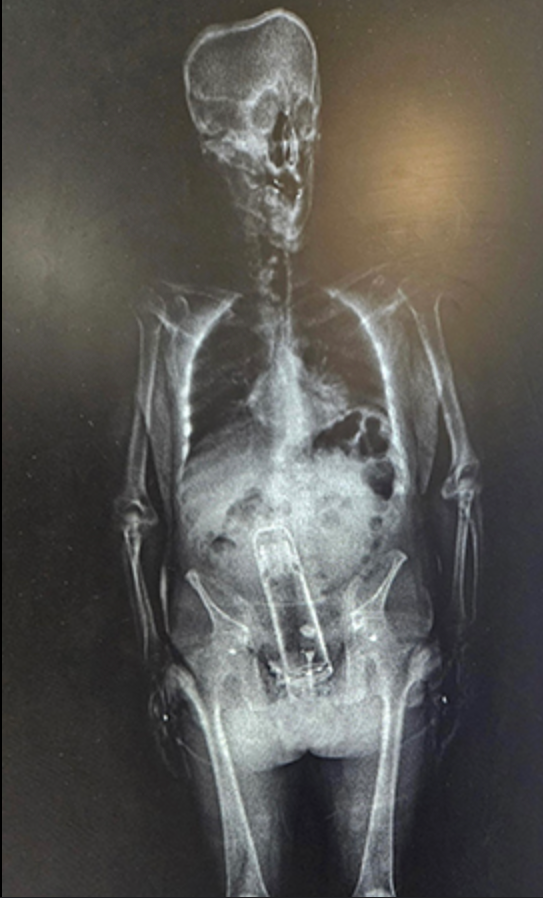

However, a routine body scan given to all prisoners revealed something even more shocking.

“You might have thought that Walter was bringing drugs into the jail,” Walter said. “He brought a thermos into the jail. That’s right.

“He put it up the exit ramp. You know what I mean?”

“We said ‘Dude! What are you doing here?’ Judge added. “He said, ‘Well, I put that inside my body.’

“He didn’t swallow it twenty-four hours earlier.”

According to the sheriff, the authorities were forced to take Frymire to a nearby hospital where he was treated by a “specialist.”